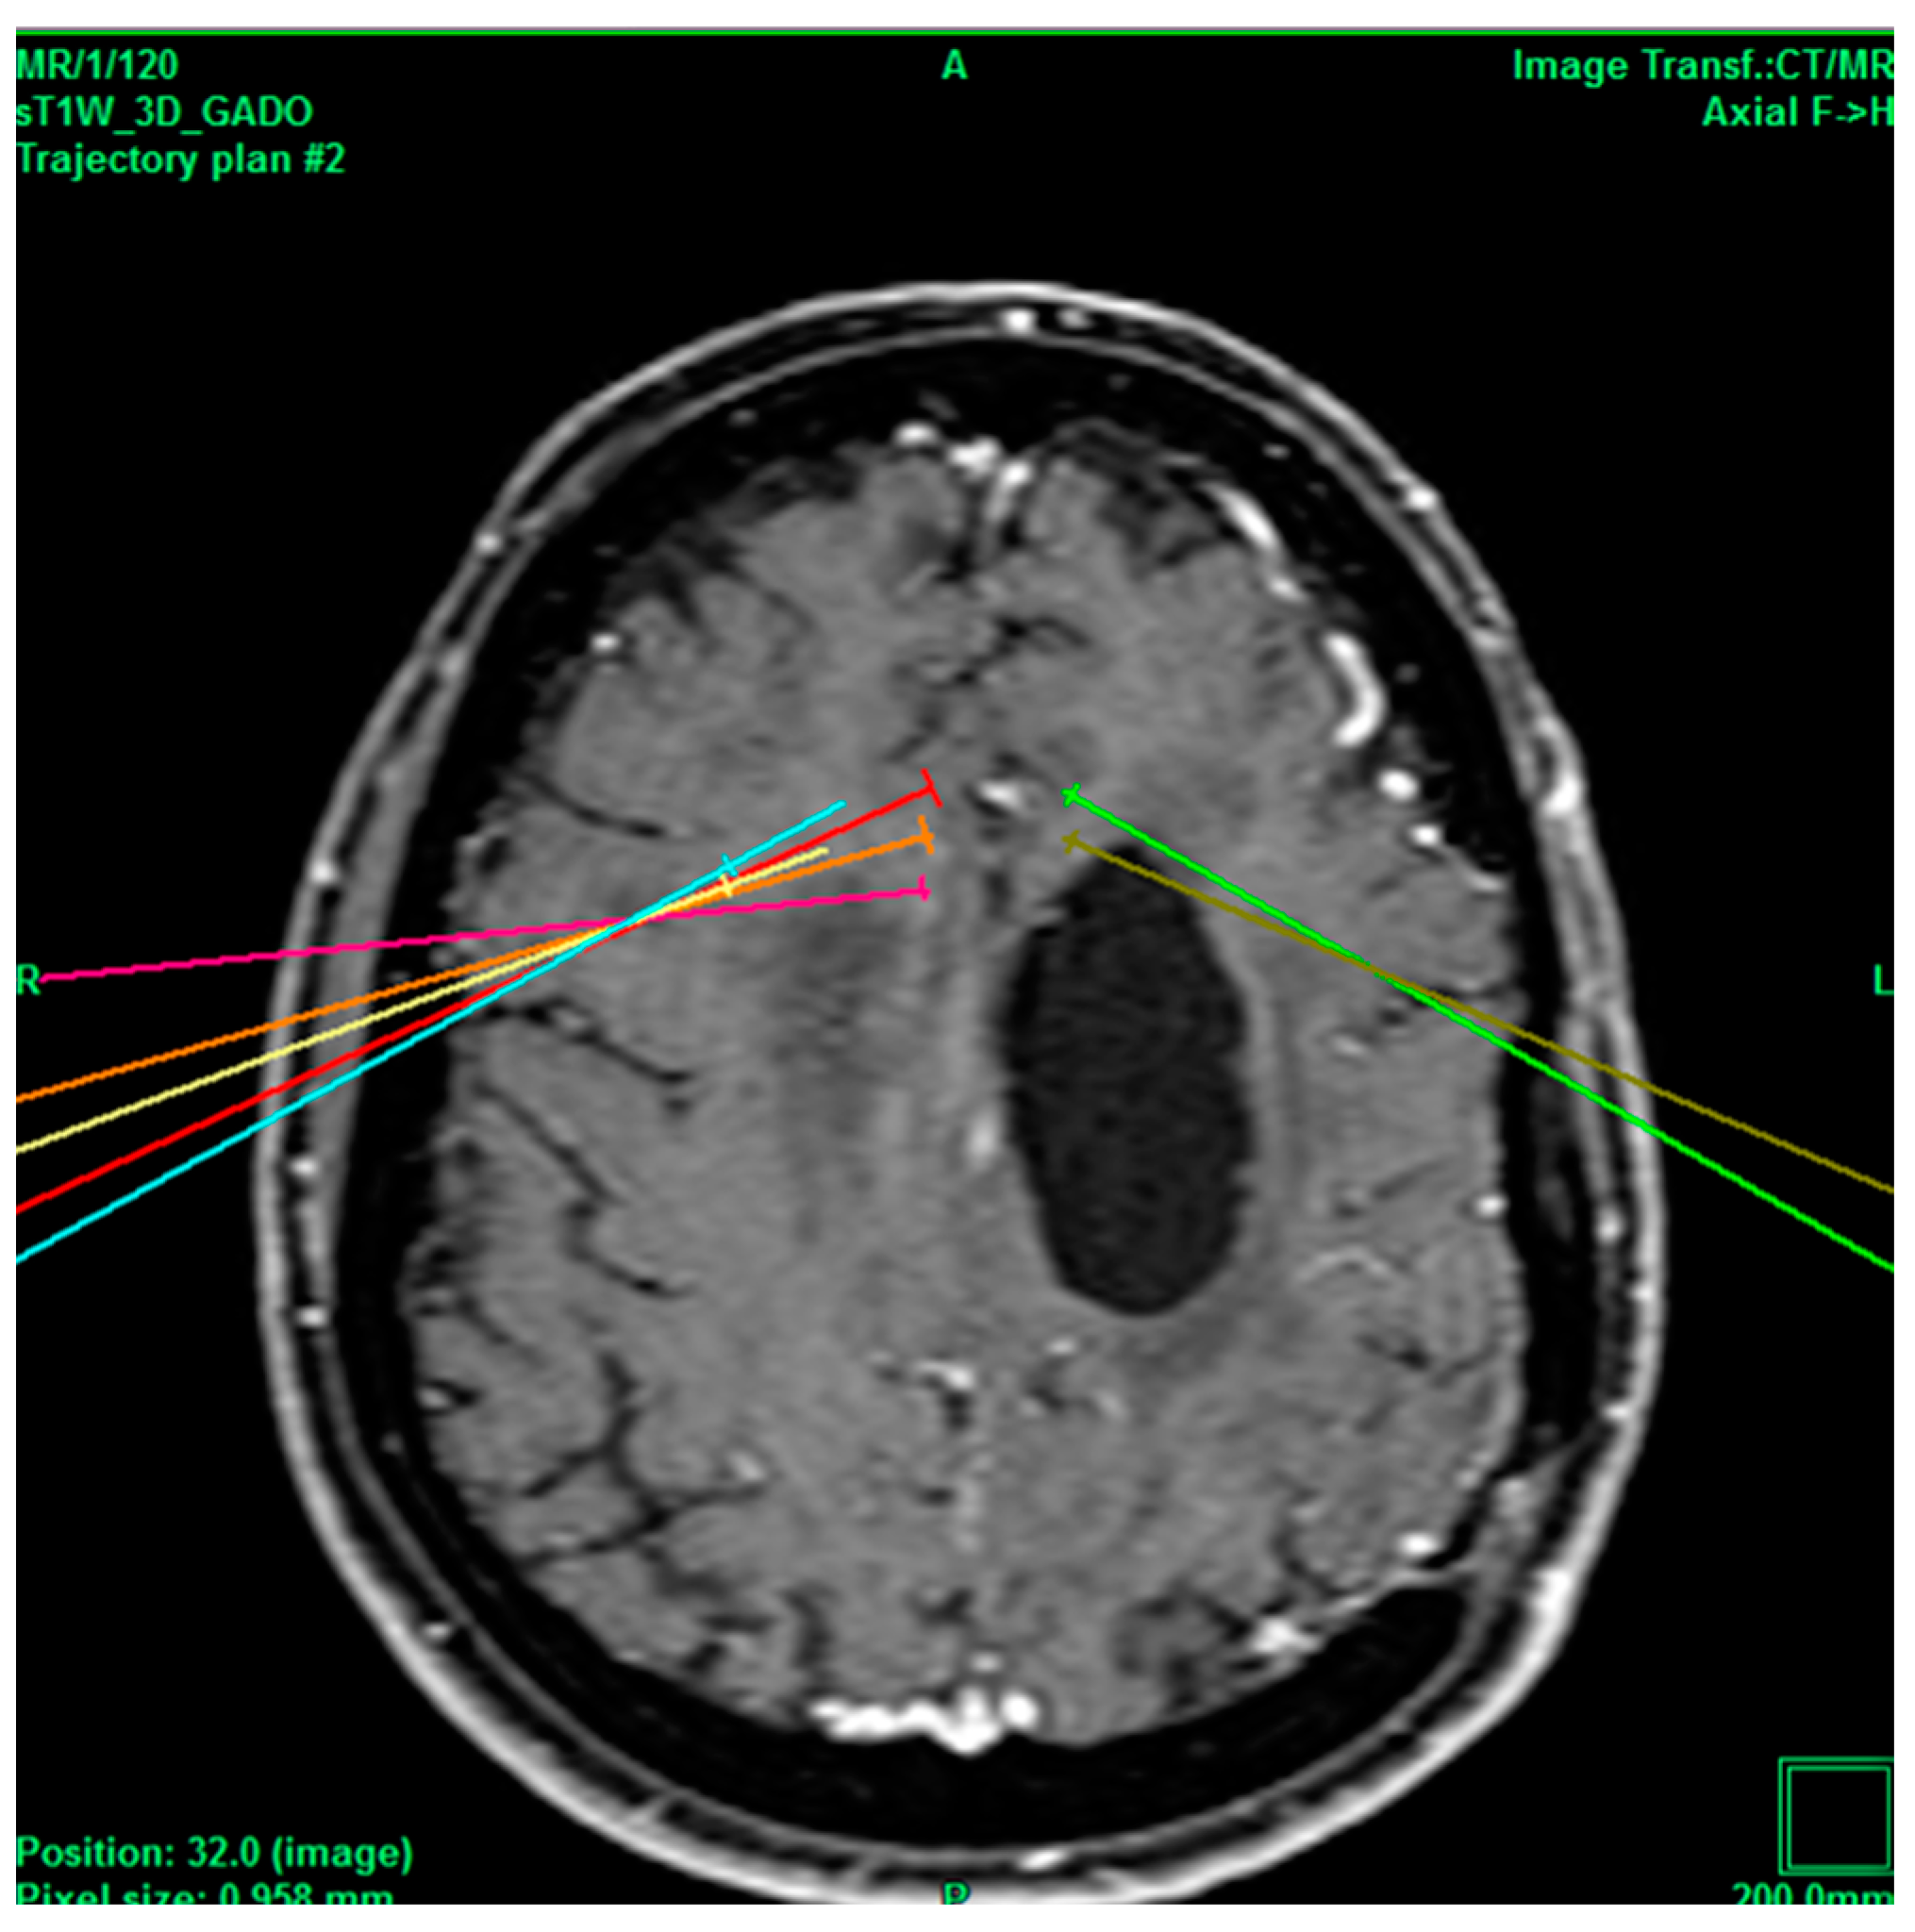

Figure 3.

Bilateral projection of cross-sectional cingulotomy from patient 2. Note hypodense region due to cavernoma.